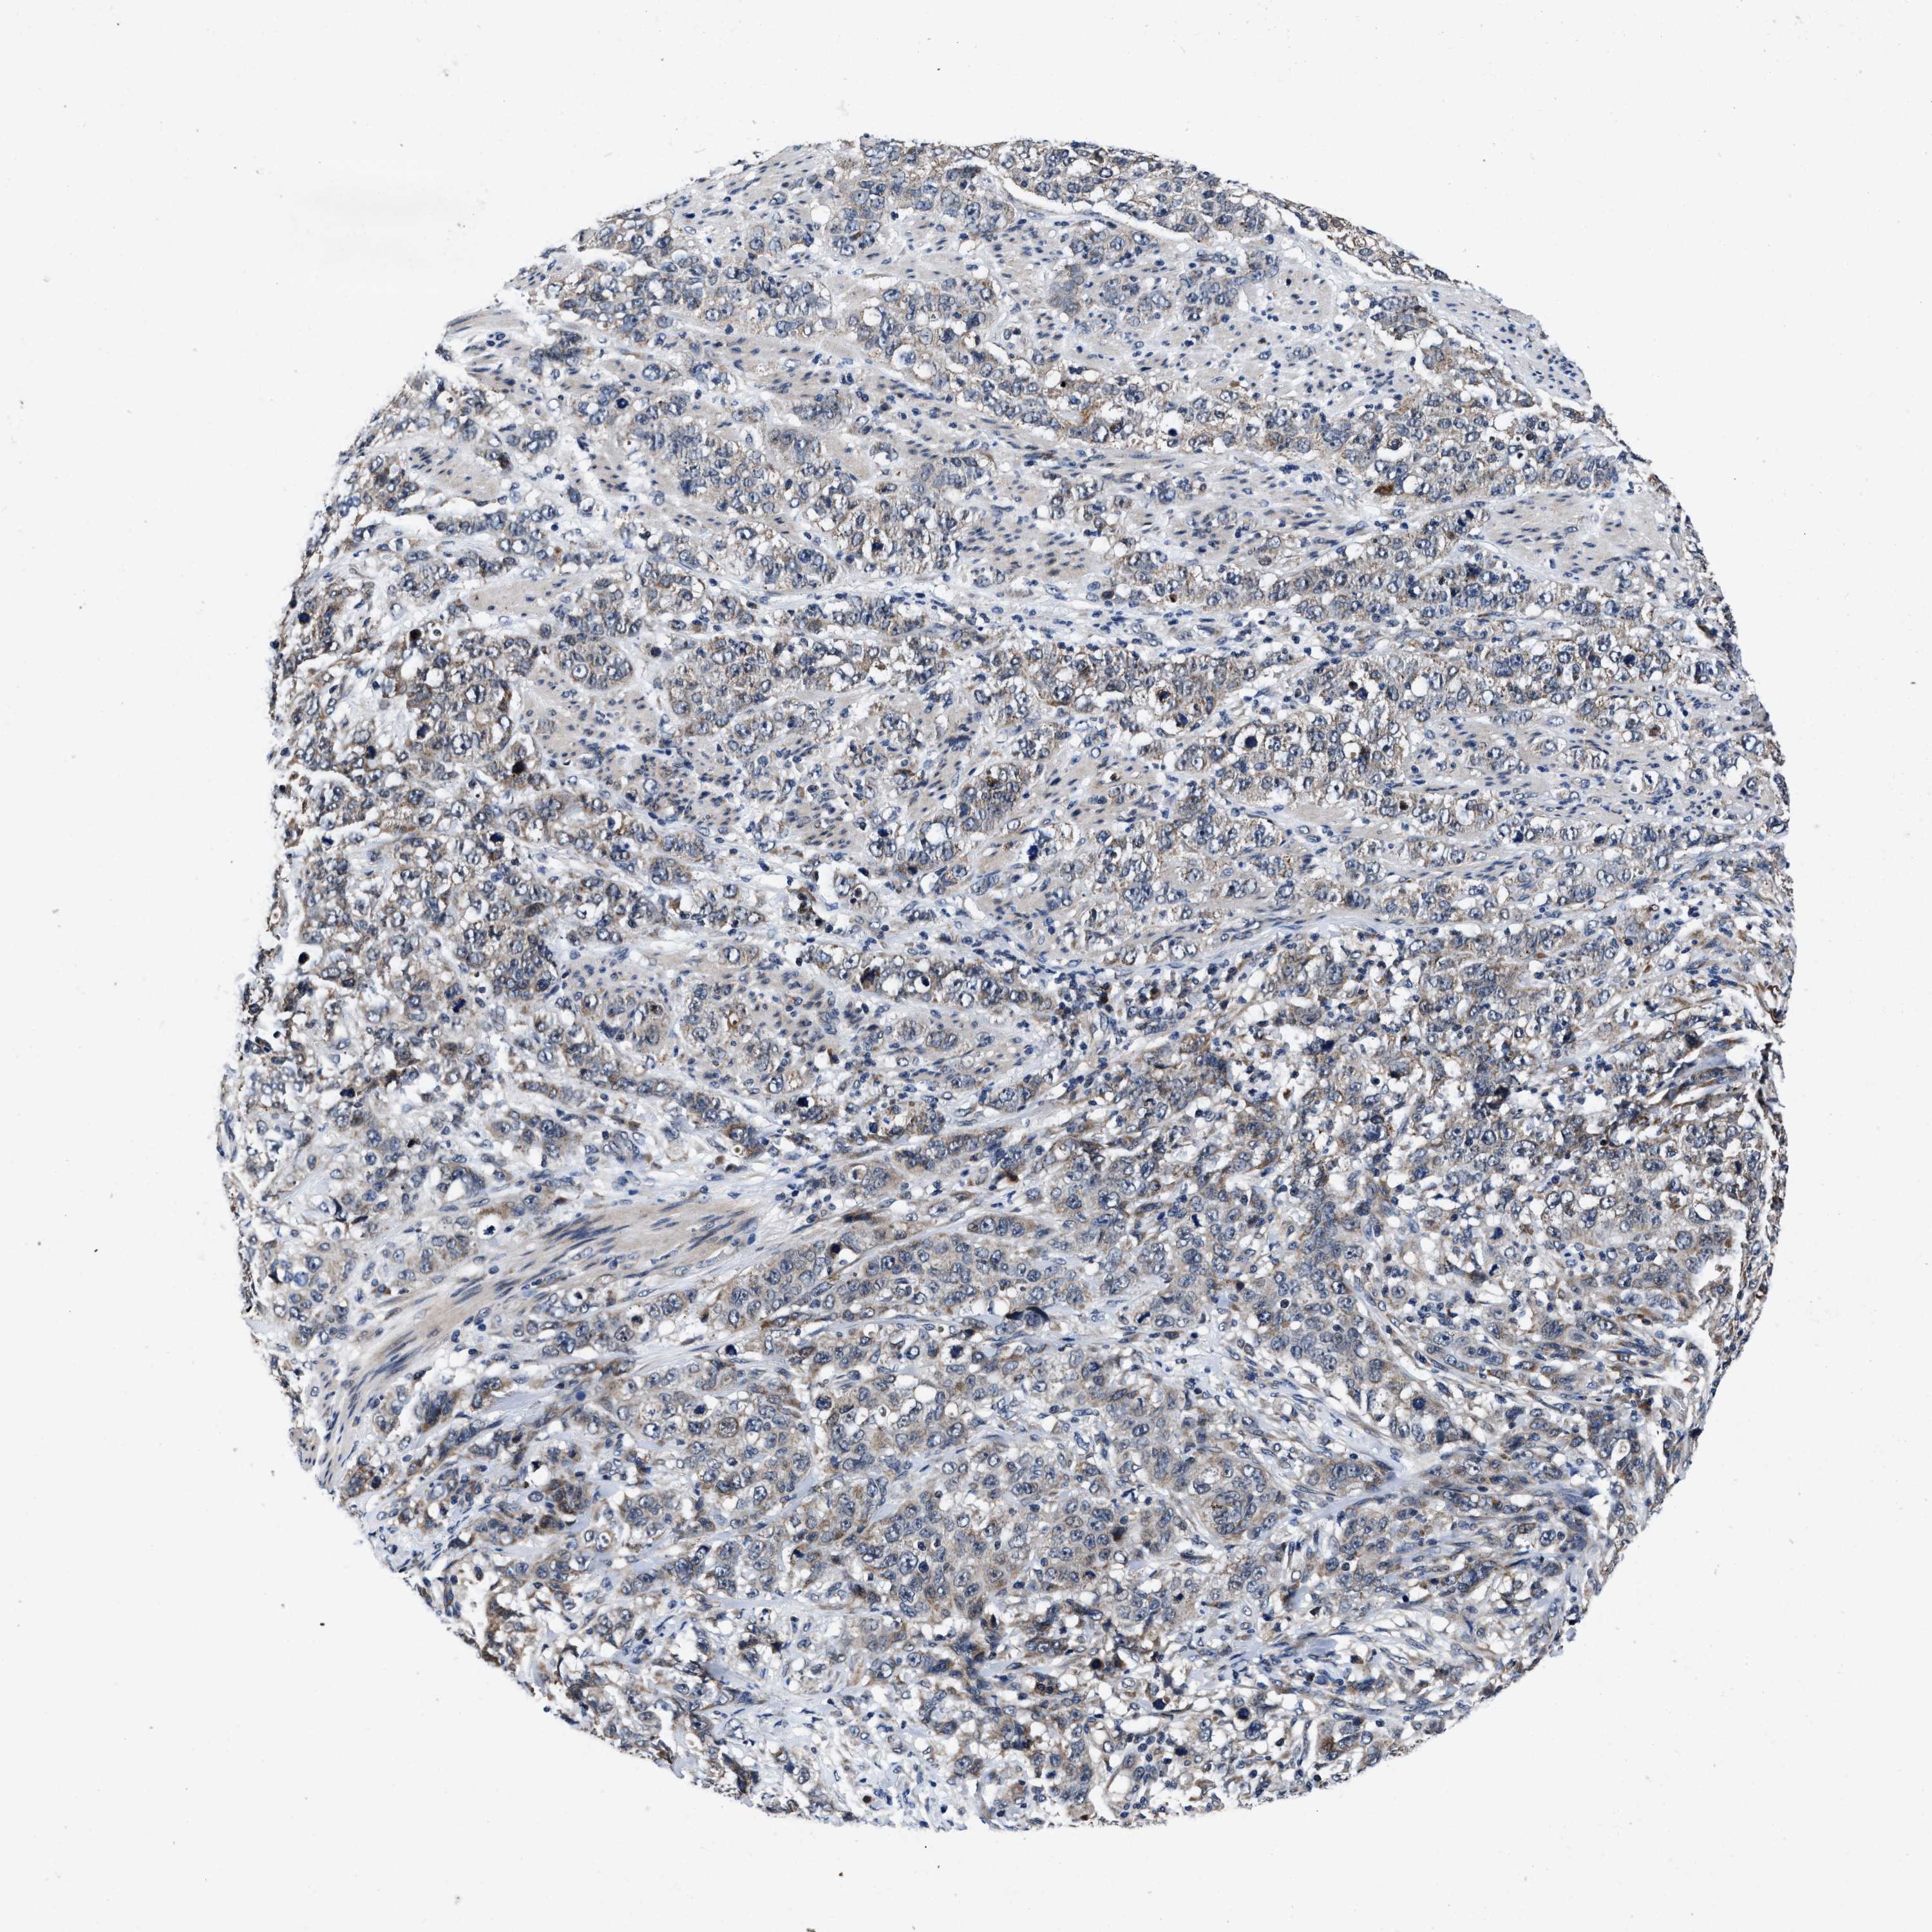

STOMACH CANCER - Protein expressioni

A mouse-over function shows sample information and annotation data. Click on an image to view it in a full screen mode. Samples can be filtered based on level of antibody staining by selecting one or several of the following categories: high, medium, low and not detected. The assay and annotation is described here.

Note that samples used for immunohistochemistry by the Human Protein Atlas do not correspond to samples in the TCGA dataset.

Antibody stainingi

Antibody staining in the annotated cell types in the current human tissue is reported as not detected, low, medium, or high, based on conventional immunohistochemistry profiling in selected tissues. This score is based on the combination of the staining intensity and fraction of stained cells.

Each image is clickable and will lead to virtual microscopy that enables deeper exploration of all samples and also displays staining intensity scores, fraction scores and subcellular localization as well as patient and tissue information for each sample.

Antibody HPA021134

Staining

High

Medium

Low

Not detected

Intensity

Strong

Moderate

Weak

Negative

Quantity

>75%

75%-25%

<25%

None

Location

Nuclear

Cytoplasmic/membranous

Cytoplasmic/membranous,nuclear

Adenocarcinoma, NOS